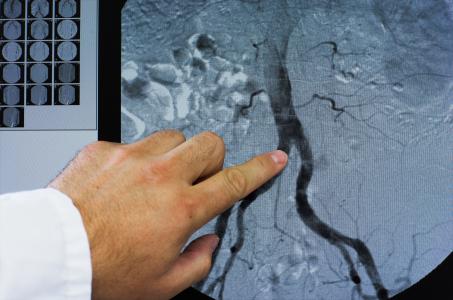

La maladie artérielle périphérique (MAP) survient lorsque les artères partant du cœur se rétrécissent en raison de dépôts de cholestérol, empêchant ainsi une circulation sanguine adéquate dans tout le corps et généralement les membres inférieurs. On estime que la MAP affecte 10 à 12 millions d’adultes âgés de 40 ans et plus aux seuls États-Unis et plus de 200 millions de personnes dans le monde.

L’étude suit et analyse les données de près de 95.000 participants âgés de plus de 50 ans atteints de MAP et ayant subi une revascularisation. Précisément, les 2 tiers des participants ont subi cette intervention chirurgicale élective pour rétablir la circulation sanguine, un tiers ayant subi une intervention chirurgicale en urgence. L’analyse constate que :

le risque d'amputation majeure chez ces patients âgés de 50 à 54 ans s’élève à 18 % 1 an après la revascularisation

- et à 29 % 5 ans après l'intervention ;

- chez les patients âgés de 80 à 84 ans, ces taux de risque s’élèvent, respectivement à 12 et 17 % ;

- parmi les patients ayant subi une revascularisation élective, le risque d'amputation reste relativement faible quel que soit l'âge du patient : 11 % pour les 50 à 54 ans et 6,5 % pour les 80 à 84 ans ;

- le risque de décès augmente cependant considérablement chez les patients plus âgés après revascularisation élective et non élective : 49 % et 59 %, respectivement à 1 et 5 ans, pour les patients âgés de 80 à 84 ans vs 13 et 17 % , respectivement, pour les 50-54 ans ;

- après une amputation les participants encourent un risque accru de décès lorsqu’ils ont subi une amputation majeure dans les 6 mois qui suivent la revascularisation.